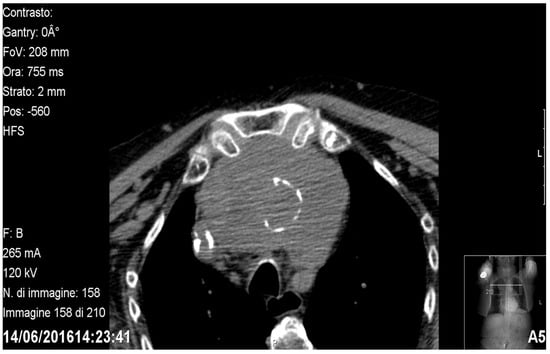

Figure 1.

Axial CT showing a prevascular retrosternal goitre.